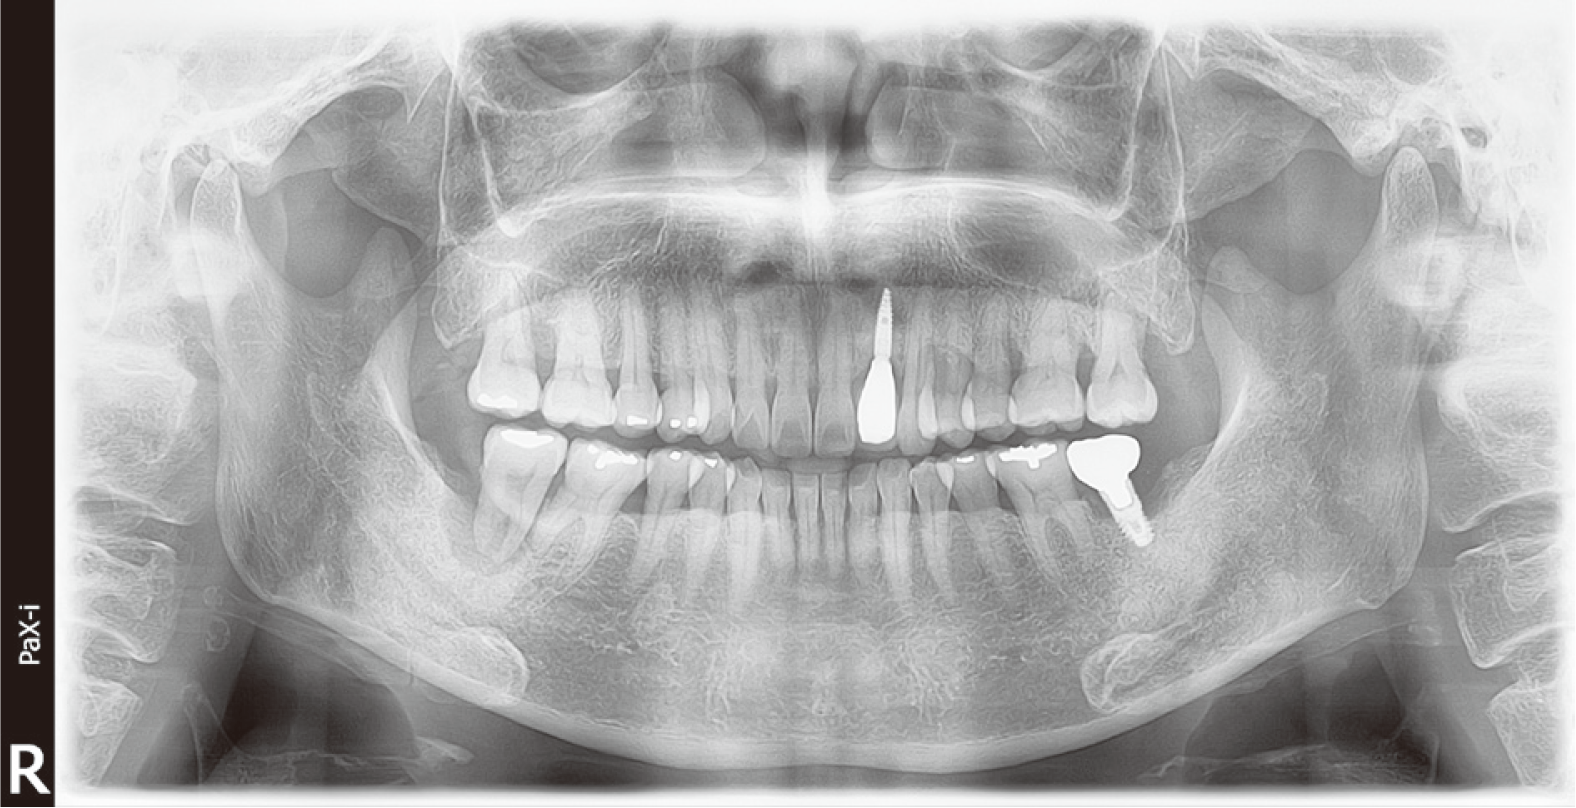

60세 남자 환자로 전체적인 치과치료를 위해 본원에 내원하였다. 환자는 의과적으로 기질성 정신장애를 진단을 받았으며, 거동이 불편하고 보행이 불가능하여 요양병원에서 입원 치료 중이었다. 정신건강의학과에서 환자의 정신장애에 대해 치료상태가 안정된 상태임을 확인한 후, 치과치료를 진행하였다. 파노라마 방사선 사진 및 구강검사에서 상악 우측 제1소구치와 제1대구치, 좌측 제제1, 2소구치, 하악 우측 제1대구치에 잔존 치근이 존재하였으며, 상악 우측 견치와 하악 좌측 견치 및 소구치에서 치아우식증이 관찰되었다(Fig. 1). 환자의 의과적 병력과 치료의 협조도, 구강위생 조절 능력 등을 고려했을 때, 가철성 보철물의 유지와 관리가 어렵다고 판단되어 고정성 보철물로 수복을 계획하였다. 예후가 불량한 상악 우측 견치, 제1소구치, 제1대구치와 좌측 제제1, 2소구치, 하악 좌측 견치, 제1소구치와 우측 1대구치를 발치 한 후, 치아 상실부위에 임플란트 식립을 하였고(Fig. 2), 골유착 기간을 거쳐 최종인상을 채득하였다. 제작한 임플란트 보철물을 장착하던 과정에서 치과의사는 하악 우측 제제1, 2소구치와 제1대구치로 이루어진 3본 지르코니아 보철물이 환자의 구강 내로 떨어뜨렸고, 떨어진 즉시 환자의 두부를 좌측으로 돌려 환자가 보철물을 삼키지 않도록 노력하였으나, 환자가 보철물을 삼키게 되었다. 환자가 보철물을 삼킨 이후 기침이나 구토 반사 등의 특이적 소견을 보이지 않았으며, 호흡상태는 양호하였다. 환자 보호자에게 보철물 장착과정에서 보철물을 구강 내로 떨어뜨렸고, 이후 삼킴이 발생하였음을 설명하였다. 그리고 삼켜진 보철물의 위치 확인을 위하여 인근 내과로 전원 의뢰를 시행하였다. 전원 의뢰된 당일, 내과에서 복부 방사선 사진을 촬영하였고, 판독 결과 보철물이 위장에 위치를 하고 있음을 확인하였다. 24시간 이후 배출될 것으로 예상되어 48시간 후 재촬영이 필요할 것이라는 회신서를 확인하였다(Fig. 3). 2일 후 환자를 내원하도록 하여 추가로 복부 방사선 사진을 촬영하였다. 방사선 사진에서 위장관 내에서 보철물 확인되었다. 환자의 거동이 불편하여 위장관 운동이 저하되어 있는 상태이기 때문에 배출이 지연될 수 있다는 의과적 소견을 회신 받았다(Fig. 4). 8일 후 환자의 복부 방사선 사진을 촬영하였으며, 보철물이 위장관에서 완전히 배출되어 체 내에 있지 않음을 확인하였다(Fig. 5). 이 후 하악 우측 제1, 2소구치와 제1대구치에 새로운 보철물을 제작하여 최종 합착(Rely-X, 3M ESPE, St Paul, USA)을 시행하였다(Fig. 6).